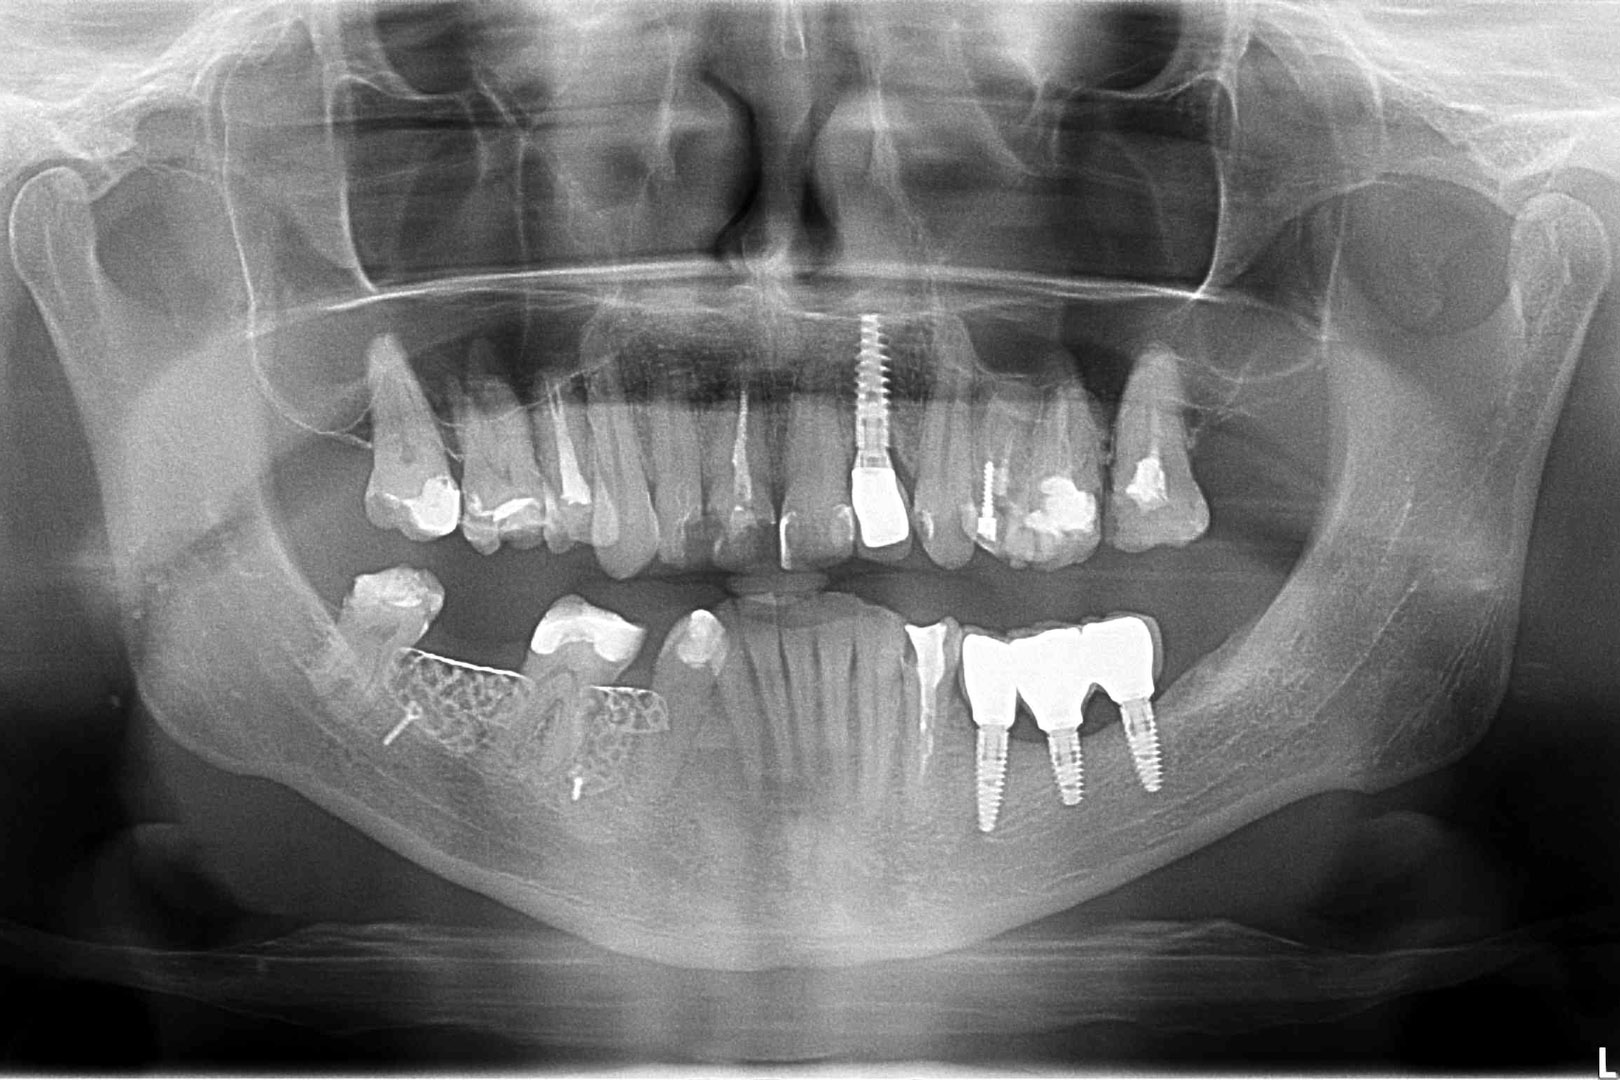

Przed podjęciem leczenia należy określić stopień zaniku kości szczęk oraz żuchwy. W tym celu przeprowadza się badanie kliniczne oraz odpowiednią diagnostykę obrazową pacjenta. Uwzględnia ona zdjęcie panoramiczne OPG jako podstawę dwuwymiarowego obrazowania podłoża kostnego oraz możliwe jest badanie tomograficzne CT lub bardziej precyzyjna tomografia stożkowa CBCT. Opcjonalnie wykorzystywana diagnostycznie tomografia pozwala na bardziej wnikliwą ocenę stopnia zaniku kości w trójwymiarowym, przestrzennym obrazie.